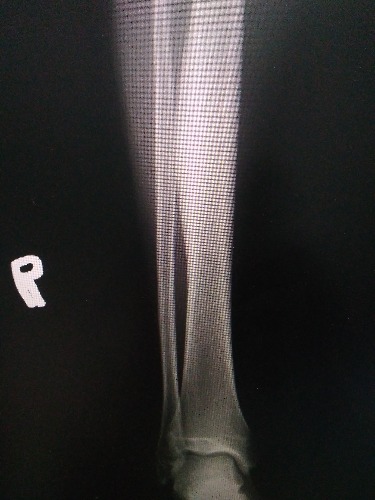

CT52923:右小腿

本帖最后由 cefcmj 于 2017-8-6 18:09 编辑 右小腿外伤后

右胫骨中下段髓腔密度增高,骨皮质、骨外膜增厚。考虑:右胫骨硬化性骨髓炎。

硬化性骨髓炎(又名Garre's病,特发性骨皮质硬化和干性骨髓炎)?

慢性骨髓炎?